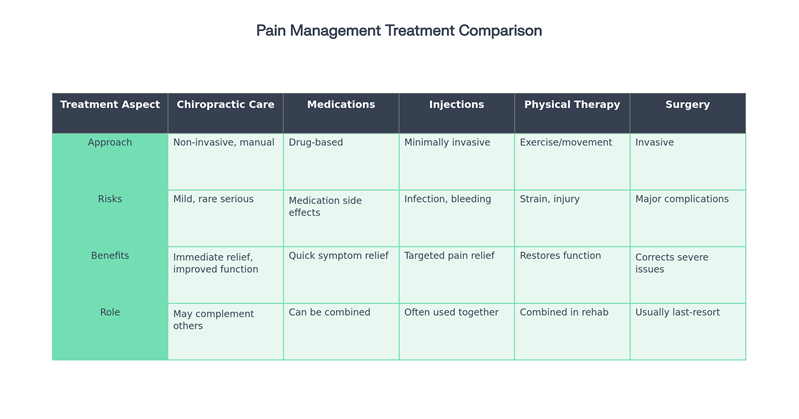

Chiropractic vs. Other Pain Management Treatments

How does chiropractic differ from physical therapy or injections?

Chiropractors focus on spinal manipulation and holistic techniques, while physical therapy uses exercise and movement, and injections provide targeted medication.